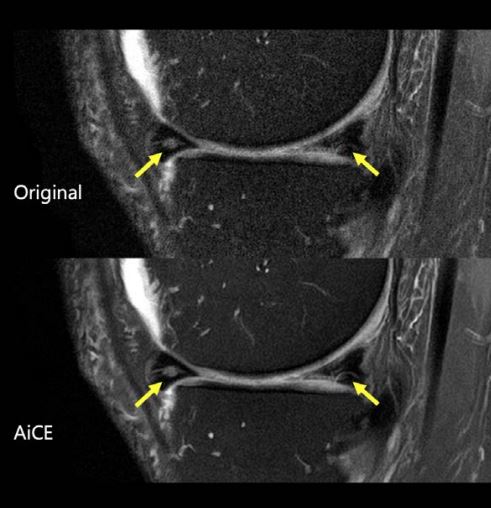

На рис. 1 показано, що AiCE навчено лише видаляти шум, зберігаючи анатомічні структури. На рис. 2 і 3 показано, що на реконструйованих AiCE зображеннях зберігаються анатомічні та патологічні особливості.

Рис. 2. Розриви меніска (стрілки) збереглися на зображенні, обробленому за допомогою AiCE.